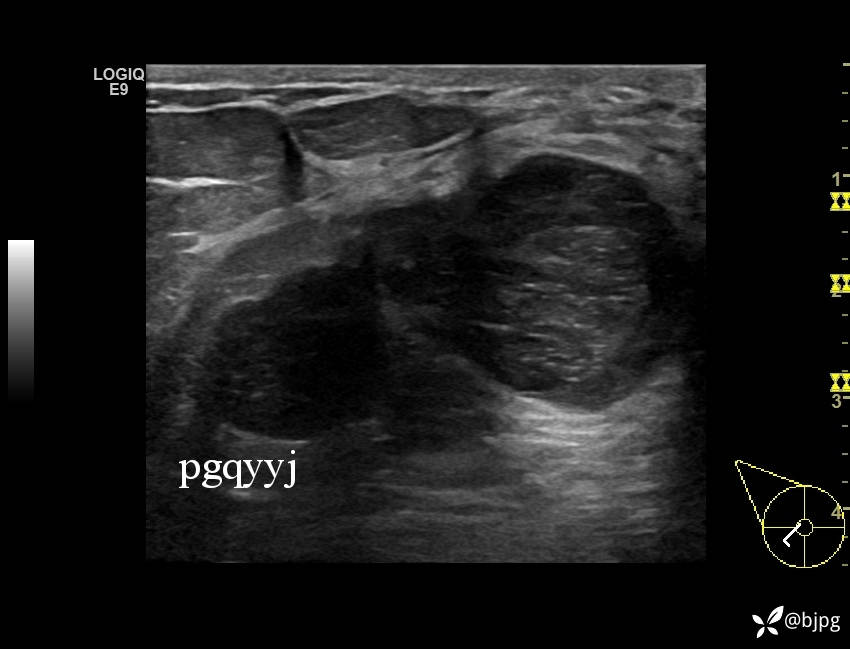

【患者信息】:女性36岁

【主诉】:发现右乳肿物一周

【检查】:超声

【临床诊断】:右乳结节,性质待定

【治疗经过及结果】:穿刺活检,欢迎同道讨论,穿刺病理数日后公布。

乳腺分叶状肿瘤 (7)